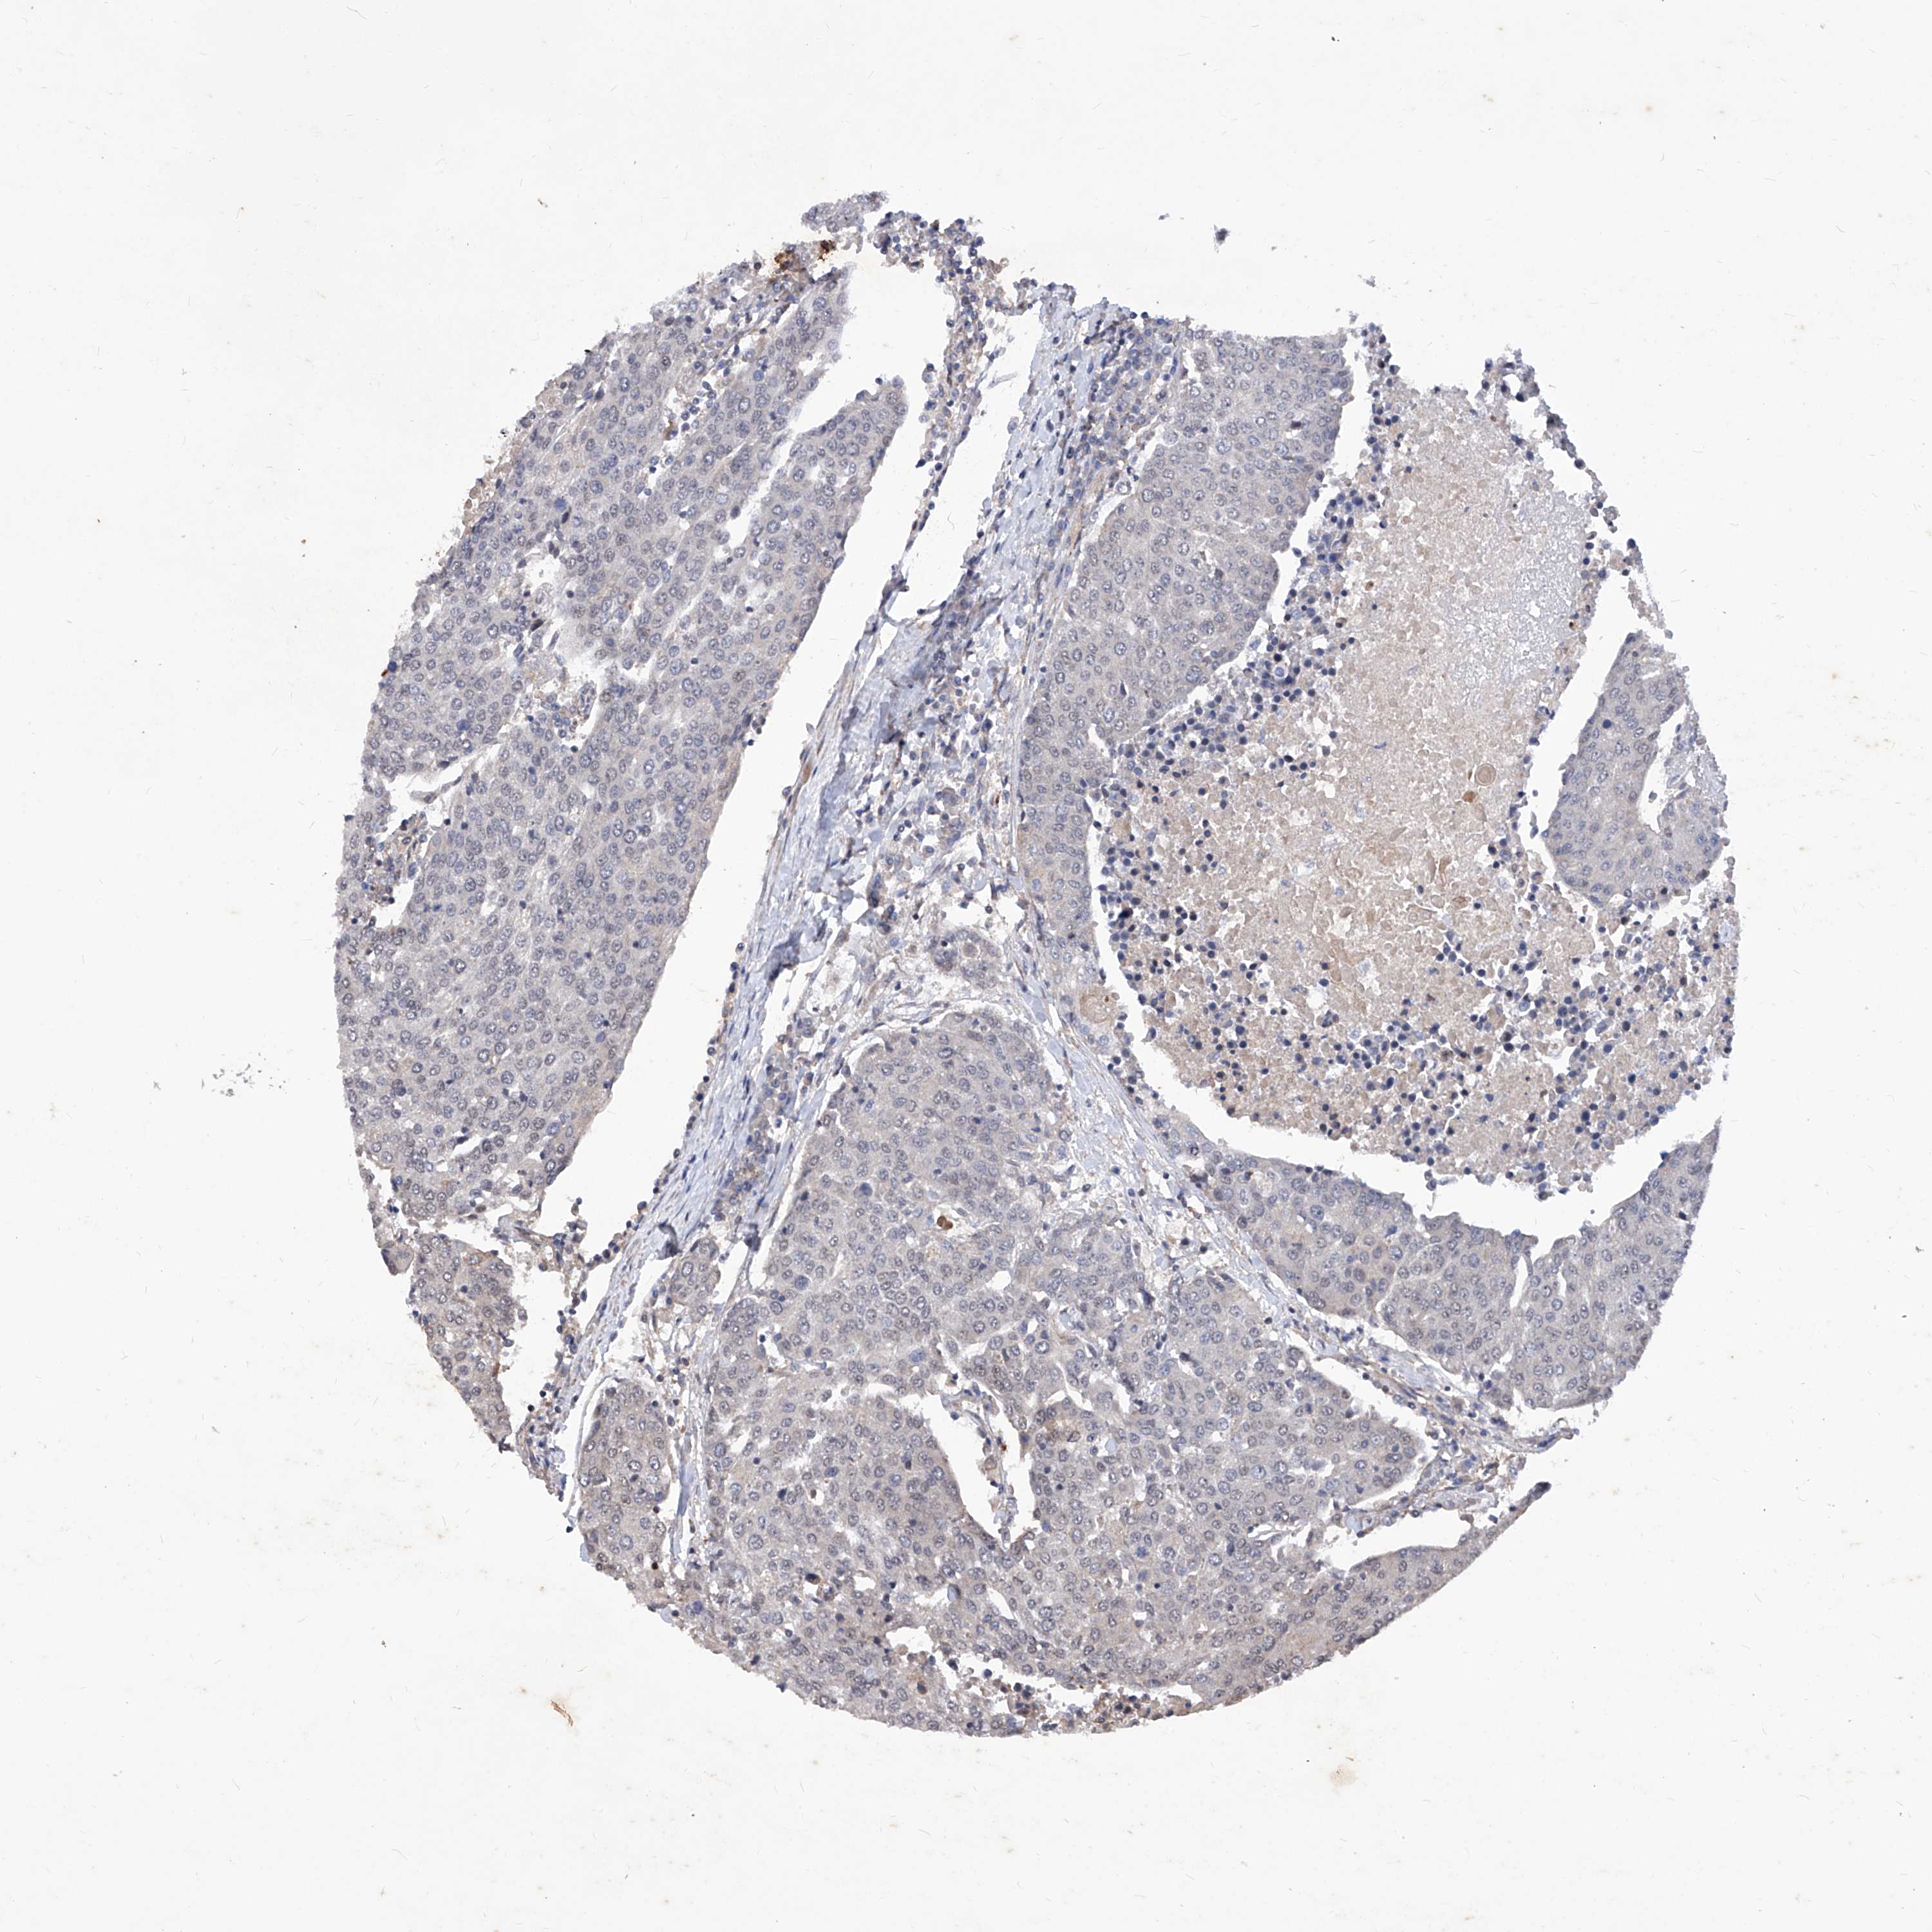

UROTHELIAL CANCER - Protein expressioni

A mouse-over function shows sample information and annotation data. Click on an image to view it in a full screen mode. Samples can be filtered based on level of antibody staining by selecting one or several of the following categories: high, medium, low and not detected. The assay and annotation is described here.

Note that samples used for immunohistochemistry by the Human Protein Atlas do not correspond to samples in the TCGA dataset.

Antibody stainingi

Antibody staining in the annotated cell types in the current human tissue is reported as not detected, low, medium, or high, based on conventional immunohistochemistry profiling in selected tissues. This score is based on the combination of the staining intensity and fraction of stained cells.

Each image is clickable and will lead to virtual microscopy that enables deeper exploration of all samples and also displays staining intensity scores, fraction scores and subcellular localization as well as patient and tissue information for each sample.

Antibody HPA029534

Staining

High

Medium

Low

Not detected

Intensity

Strong

Moderate

Weak

Negative

Quantity

>75%

75%-25%

<25%

None

Location

Nuclear

Cytoplasmic/membranous

Cytoplasmic/membranous,nuclear

Urothelial carcinoma, Low grade

Urothelial carcinoma, High grade